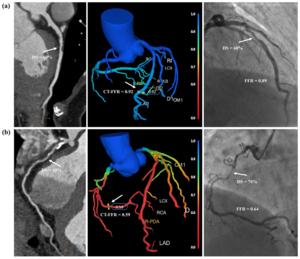

张龙江教授与卢光明教授发表首个全自动化CT-FFR临床应用研究:该3阶段研究的中心示意图 (IMAGE) Science China Press Caption 该研究设计与主要结果 Credit ©《中国科学》杂志社 Usage Restrictions Use with credit. License Original content Disclaimer: AAAS and EurekAlert! are not responsible for the accuracy of news releases posted to EurekAlert! by contributing institutions or for the use of any information through the EurekAlert system.